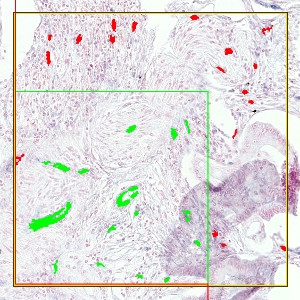

Automated detection of ROI. The area surrounded by the green line is the ROI. Areas that are grayed out are not part of the ROI.

The auxiliary APP, ’01 ROI Detect’ can be used to automatically detect the region of interest (ROI). The APP utilizes a Bayesian classifier to detect the tissue areas of interest (see FIGURE 1). In some cases, the operator may subsequently have to manually remove certain irrelevant tissue areas to be excluded from the microvessel quantification, e.g. normal and/or necrotic tissue regions.

For an optimal outcome of this APP, it is recommended to start by using the auxiliary APP to detect the ROI (see Auxiliary APPs). This is used for outlining the region of interest (ROI) by identifying the tissue area and discarding staining artifacts (see FIGURE 1).